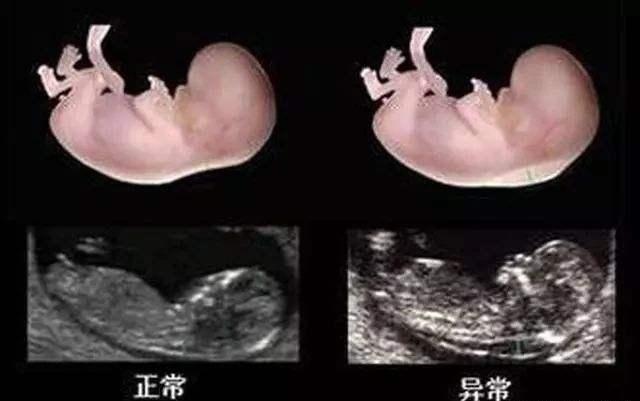

NT检查,是一个产检项目的简称,全称是:nuchal translucency,指的是“颈项透明层”,但并不是看孕妇的脖子,而是针对胎儿的检查,通过B超测算出肚子里胎儿的颈椎厚度(颈椎水平矢关切面皮肤至皮下软组织之间的最大厚度),它是整个孕期产检项目中重要的一项。

前面也说了,NT检查主要是检测胎儿颈部透明层的厚度,然后根据这个厚度数值评估胎儿的发育情况,主要是为了初筛查“是否有患唐氏综合征的可能”,算是孕期第一次排畸检查。

唐氏儿NT值大多数不正常,但NT值高不一定就是唐氏儿,只是说明胎儿有患“唐氏综合征”的风险大,概率在60%-70%,需要做进一步检查确认和排查。

其次,做B超查出来的“颈后透明带厚度”的准确度由很多因素决定,如B超医生的水平、扫描仪的精确度等,而且如果取的不是正矢位,也会有误差,因此检查结果并不能保证100%准确。